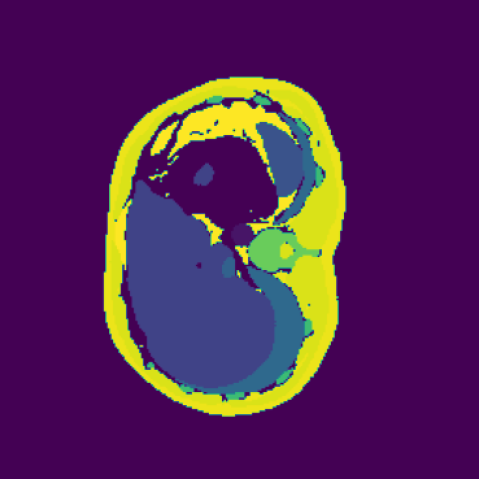

The hypothesis of this experiment is that if the synthetic images generated by our model resemble real medical images in distribution, a segmentation network trained on real data should yield similar performance on synthetic data. By comparing the segmentation results across real and synthetic images, we can quantitatively assess the structural fidelity and semantic consistency of the generated data. The results confirm that segmentation performance on synthetic images is highly comparable to that on real images, indicating that our model successfully captures anatomically relevant structures. This suggests that synthetic data are not only realistic but also potentially beneficial as an augmentation strategy to improve segmentation tasks. Visualizations of the segmentation output are presented in Figure 6.

The goal of our research is not to generate fancy or visually appealing images, but rather to produce images that are useful for downstream tasks. Our focus is on creating synthetic data that have small domain gap with real data, helping to address the bottleneck of data scarcity in the field of machine learning for medical imaging. By generating images that are meaningful for specific tasks, we aim to improve the performance of models in clinical applications, ultimately driving advancements in medical image analysis where labeled data are often limited. In this experiment, We first train a 3D segmentation network using the images and the corresponding semantic maps from training set of the real Duke Breast dataset. The model and training details can be found in the Appendix B. The purpose is to allow the network to learn how to segment anatomical structures from real MRT data. After completing the training phase, we evaluated the segmentation network on four different datasets as shown in Table 2: (1) real images from the Duke Breast dataset training set, (2) real images from the Duke Breast dataset test set, (3) synthetic images generated by our SegGuidedDiff model [26] using semantic maps from the Duke Breast test set, and (4) synthetic images produced by our Med-LSDM model based on the same semantic maps. By evaluating the segmentation results on different real and synthetic images, we aim to investigate the effectiveness of the generative model in producing realistic images that could yield similar segmentation results to real data, suggesting that real and synthetic images lie in similar regions of the data distribution.

Table 2 presents the segmentation performance, measured by the Dice similarity coefficient averaged over all semantic classes, across different data sources. The real training data achieve the highest Dice score of 0.750, which indicates that the segmentation model achieves a 75% overlap between the predicted region and the ground truth. When tested on the real test set, the score falls slightly to 0.715, indicating good generalization.

In contrast, the segmentation result of synthetic data generated by SegGuidedDiff using 2D semantic map slices shows significantly lower performance (Dice = 0.602). Notably, SegGuidedDiff generates images slice-by-slice in 2D without modeling the full 3D spatial context. As a result, the synthesized volumes often suffer from inter-slice inconsistencies and unrealistic spatial structures, which negatively impact the downstream segmentation performance.

Our Med-LSDM-generated data, in contrast, achieves a Dice score of 0.70964, which is much higher than SegGuidedDiff and closely approaches the real data test performance. This indicates that our method’s 3D generation strategy successfully captures anatomical coherence across slices and produces realistic volumetric data. It is also important to note that the synthetic volumes are directly saved in NIfTI format without any post-processing, demonstrating the practical applicability and robustness of our framework.